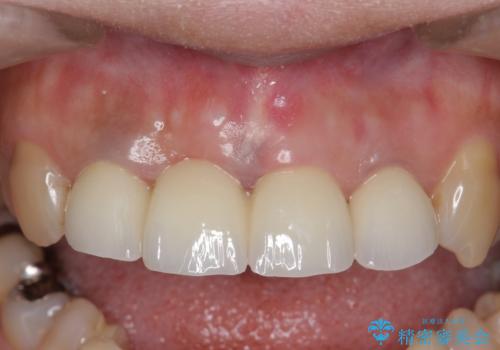

前歯の補綴ではオールセラミッククラウンを希望される患者様が多いですが、オールセラミッククラウンの中でも、エコノミー、スタンダード、スペシャル、エクセレントとランクがあります。

その中でも特に審美性が高いのがスペシャル、エクセレントです。スペシャル、エクセレントは口腔内写真をもとに熟練の技工士が、患者様の口腔内に合わせたオーダーメイドのクラウンを製作致します。